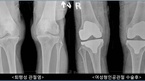

[건강 칼럼] 55세 이상 고령인구 10명 중 8명 정도가 앓고 있는 것으로 보고되는 관절염. 특히 퇴행성 관절염은 연골이 닳아 없어지면서 통증이 생기는 흔한 관절 질환이다. 주로 체중을 많이 받는 무릎관절, 고관절 등에서 자주 발생하고 상대적으로 가사노동을 많이

- 수술 환자의 94.1% “만족한다”일생을 살면서 무릎관절은 다치지 않더라도 닳을 수밖에 없다. 인생의 굴레, 노동의 훈장 같은 무릎 관절염. 성인병처럼 완치하기는 어렵지만 잘 관리해서 살면 생활에 크게 문제 되지 않아 ‘관절’에 대한 관심은 적었던 것